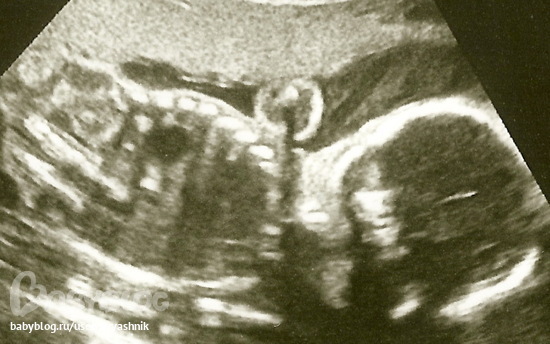

24 недели (не очень понятно отсканировалось, но тут тоже достоинство видно). Лежит полубоком лицом к "публике" и все нараспашку))) На бумажной копии хорошо видно.

Ну там написано Male))) Я там на УЗИ видела, а на фотке сама не могла найти, муж показал) Ну ему виднее)) Там стрелочка есть)) Ножки, тазовые косточки и над ними писюн торчит)) К нему стрелочка. Маленькое все, тк масштаб маленький.